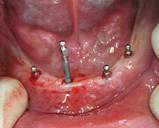

) Протезирование на имплантах

Рис 9